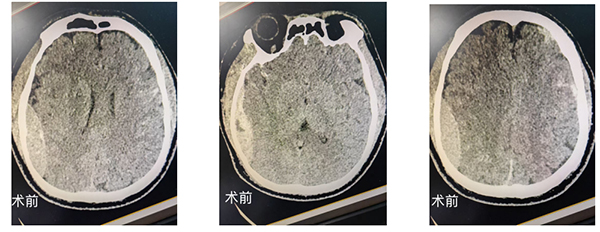

急诊医护团队第一时间开展清创缝合,但患者随即出现神志昏迷、一侧瞳孔散大,左:右约为直径2mm:5mm,对光反射消失,伴随尿失禁、频繁呕吐等症状,呕吐物带有浓烈酒臭味。神经外科值班医生张腾飞接到急会诊通知后,火速赶到现场,并向神经外科执行主任胡业帅汇报,胡主任和李志东医生也连夜驱车驰援。CT检查结果印证了最坏的预判:患者存在右侧颞顶硬膜外血肿、左侧半球弥漫性出血及骨折,颅内压力持续升高,随时可能因脑疝危及生命。